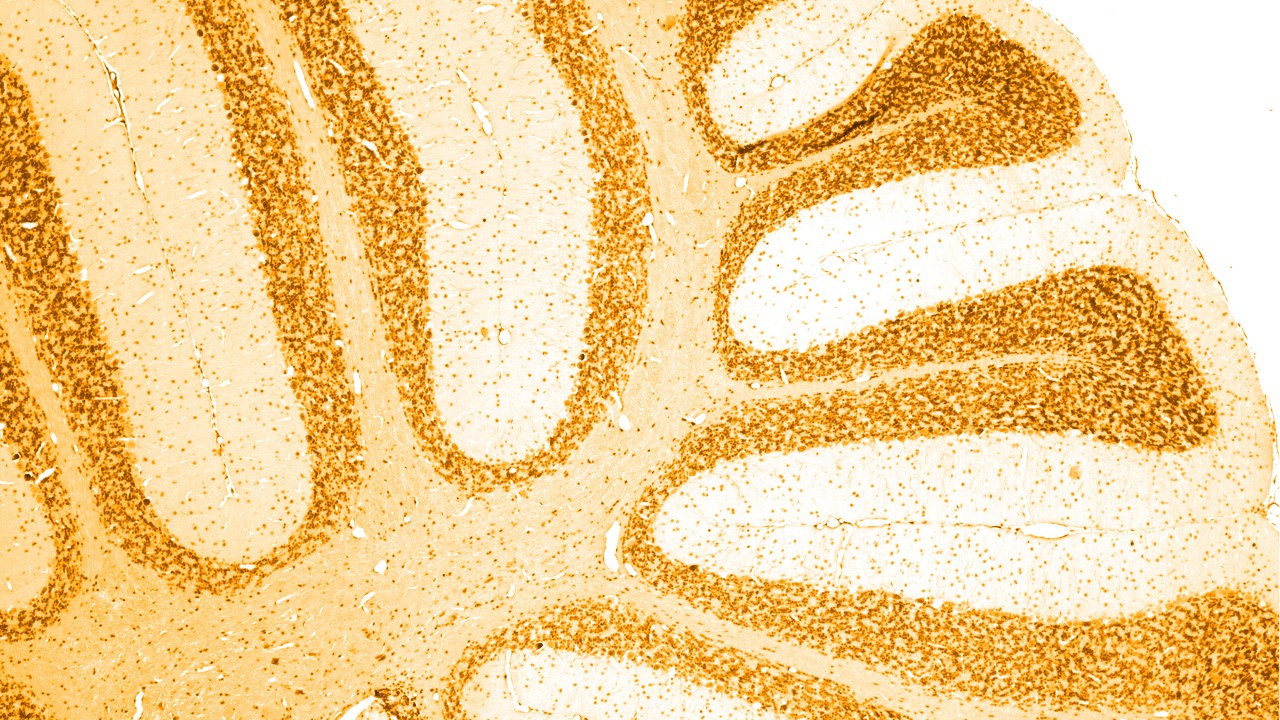

There are a number of different causes of dementia, of which the most common is Alzheimer’s disease, linked with the build-up of abnormal ‘amyloid plaques’ and ‘tau tangles’ in the brain. Certain other types of dementia also have an abnormal build-up of tau protein in the brain; as a group, these are termed ‘tauopathies’.